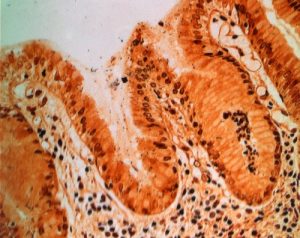

Schistosomen und H. pylori: Co-Infektion verändert Immunantwort23. September 2019 Elektronenmikroskop-Aufnahme eines Pärchenegels. Infektionen mit diesen Parasiten können zu Leberzirrhosen führen. (Bild: © Clarissa Prazeres da Costa/TUM) Ein Team der Technischen Universität München (TUM) hat nach eigenen Angaben erstmals untersucht, welche Auswirkungen eine gleichzeitige Infektion mit Schistosomen und dem Bakterium Helicobacter pylori hat – bei Menschen in manchen Regionen der Welt keine Seltenheit. Dabei zeigte sich ein komplexes Wechselspiel: Unter anderem werden negative Auswirkungen des jeweils anderen Erregers abgeschwächt. Weltweit sind rund 240 Millionen Menschen an Bilharziose erkrankt. Die Erreger sind Würmer der Gattung Schistosoma, auch Pärchenegel genannt. Die Parasiten gelangen meist aus dem Wasser in Seen, Teichen oder Flüssen in den menschlichen Körper. Im Körper werden Würmer, Larven und Eier über den Blutkreislauf in verschiedene Organe transportiert. Bei der Art Schistosoma mansoni ist besonders die Leber betroffen, dort können sie Zirrhosen hervorrufen. Mit H. pylori ist in Deutschland jeder dritte Mensch infiziert, weltweit sogar jeder zweite. Wo ein Befall mit Schistosomen vermehrt auftritt, wie in manchen afrikanischen Ländern südlich der Sahara, sind Co-Infektionen mit H. pylori häufig. Ein Team um Prof. Clarissa Prazeres da Costa und Prof. Markus Gerhard vom Institut für Medizinische Mikrobiologie, Immunologie und Hygiene der TUM hat anhand von Mäusen erstmals untersucht, was bei einer Co-Infektion von H. pylori und Schistosoma mansoni geschieht. Mit Helicobacter pylori (dunkle Punkte) infiziertes Magengewebe. Infektionen können zu Magengeschwüren und Krebs führen. (© Markus Gerhard/TUM) T-Zellen werden umgeleitet Bei einer Bilharziose folgt auf die Infektion eine akute Phase, die nach ungefähr fünf Wochen in eine chronische Phase übergeht. In ihrer Studie konnten Prazeres da Costa und Gerhard zeigen, dass bei einer Co-Infektion in der akuten Phase der Bilharziose weniger T-Zellen im Magen zu finden sind. Bei einer alleinigen Infektion mit H. pylori treten diese Immunzellen dort verstärkt auf und fördern Entzündungen. „Wir nehmen an, dass durch die Bilharziose verstärkt Chemokine in der Leber gebildet werden. Diese wirken wie ein Lockstoff auf die T-Zellen und leiten sie gewissermaßen dorthin um“, sagt Gerhard. Dadurch komme es im Magen zu weniger Entzündungen. Dieser Effekt klingt jedoch ab, wenn die chronische Phase beginnt. Während diese Phase bei einer alleinigen Schistosomen-Infektion oft mit Leberschäden verbunden ist, sind diese bei Co-Infektionen seltener. Bei ihren Untersuchungen stellten Prazeres da Costa und Gerhard im Blut von Mäusen, die mit den Bakterien infiziert waren, erhöhte Mengen des Botenstoffs IL-13dRa2 fest. „IL-13dRa2 kann vor Zirrhosen schützen und die Gewebsveränderungen sogar umkehren“, sagt Prazeres da Costa. „Wir glauben deshalb, dass sie entscheidend dazu beitragen, dass bei einer Co-Infektion weniger Leberzirrhosen auftreten.“ Mögliche Auswirkungen auf Impfungen Im Alltag infizieren sich viele Betroffene immer wieder aufs Neue mit Schistosomen, weil sie wiederholt mit von Würmern befallenem Wasser in Kontakt kommen. „Dadurch ist die Umleitung der T-Zellen in die Leber nicht zeitlich begrenzt – chronische und akute Phase existieren gleichzeitig“, erläutert Prazeres da Costa. Die Wechselwirkungen bei einer Co-Infektion mögen zunächst nach einem positiven Nebeneffekt klingen: Betroffene leiden zwar an zwei Krankheiten, dafür sind die negativen Auswirkungen scheinbar abgeschwächt. „Co-Infektionen können aber zusätzliche Konsequenzen haben. Beispielsweise könnte die veränderte Immunantwort die Wirksamkeit von Impfungen einschränken“, sagt Gerhard. „Von Co-Infektionen sind gerade in ärmeren Regionen viele Menschen betroffen“, fügt Prazeres da Costa hinzu. „Wir brauchen dringend weitere Studien zu ihren Effekten und zu Möglichkeiten, mit diesen umzugehen, zum Beispiel um neue, wirksamere Impfstrategien zu entwickeln.“